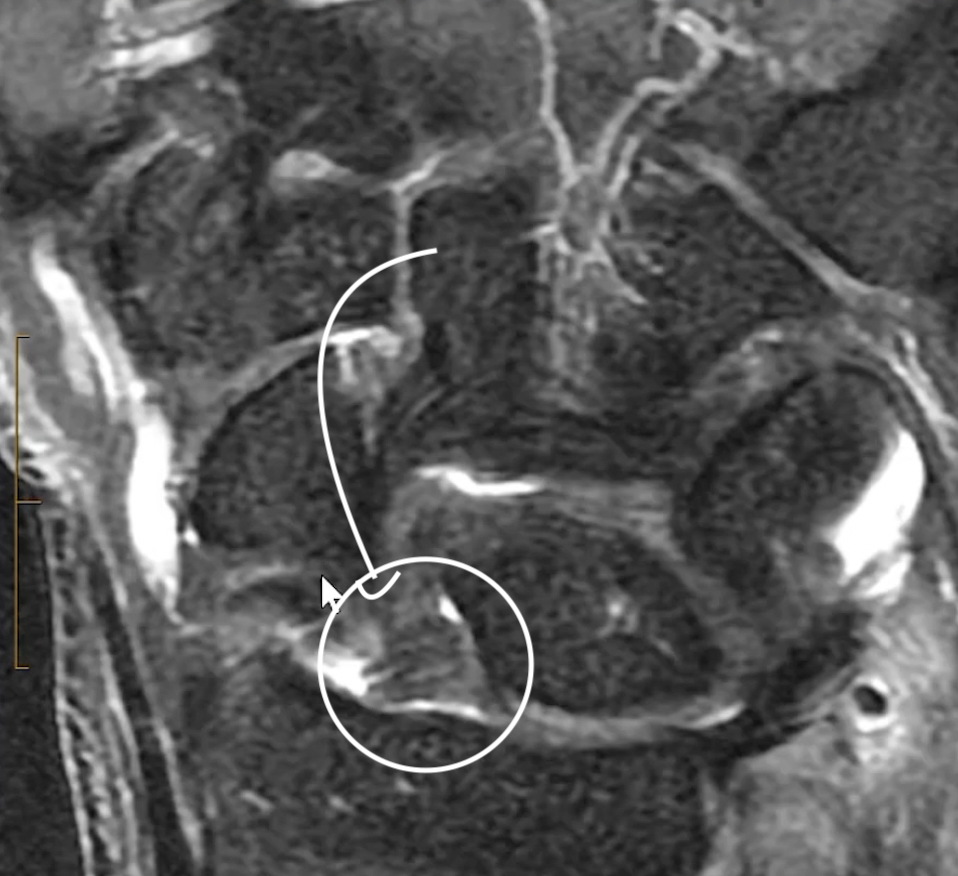

Scaphoid Stabilizers

• Scapho-lunate ligament

• Scapho-traezial-trapezoid ligament

• Very thin lines between these bones that is very hard to see

• SLING ligament (image below)

• Radio-scapho-capitate ligament

• Arises from mid radius to attach to capitate with debated attachment or overlying of scaphoid